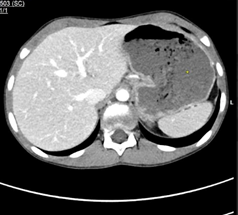

Fig  1: Axial image of IV contrast enhanced CT scan of the abdomen demonstrates gastric dilatation.

The tight and sharp aortomesenteric distance and angle respectively along with the gastric and duodenal dilatation are in favour of superior mesenteric artery syndrome.

Figure 1